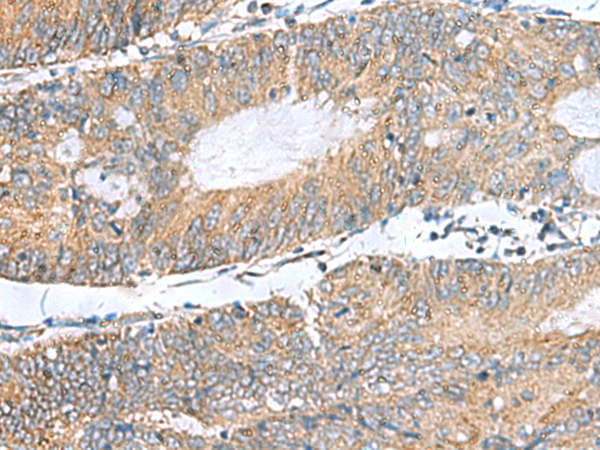

IHC (Immunohiostchemistry)

(Immunohistochemistry of paraffin-embedded Human colorectal cancer tissue using NFKB1 Polyclonal Antibody at dilution of 1:50(×200))